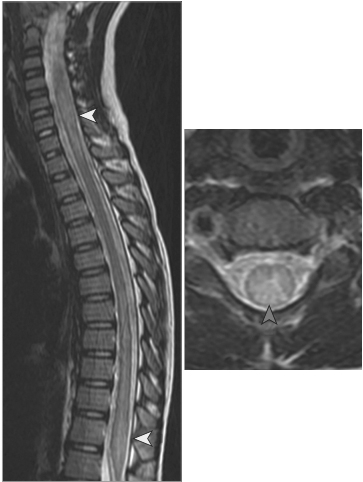

NMOSD MOG Ab Disease Sarcoidosis Paraneoplastic Dural AVF Cord Infarction Cervical Spondylosis